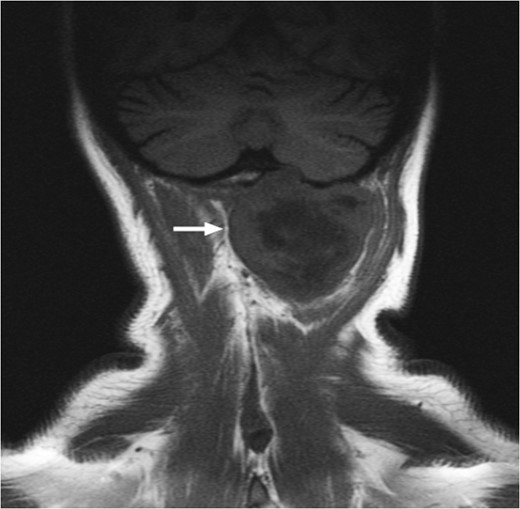

T1-weighted MRI showing the lesion in the posterosuperior aspect of the left neck arising at the level of C1, eroding through the C1 vertebra and displacing the thecal sac.

T1-weighted MRI showing the lesion eroding through the left basioccipital skull, impinging the dura overlying the left cerebellum.